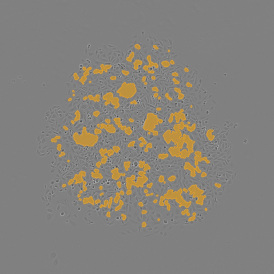

The Bone Tissue Analysis Goldner App allows for the detection of mineralized bone tissue and osteoid based on Goldner-stained bone tissue sections. The App assesses parameters such as BV (bone volume), TV (trabecular bone volume), OV (osteoid volume), OV/BV, OV/TV, OS (osteoid surface), BS (bone surface length), and the mean of osteoid width and thickness.

App Category 2